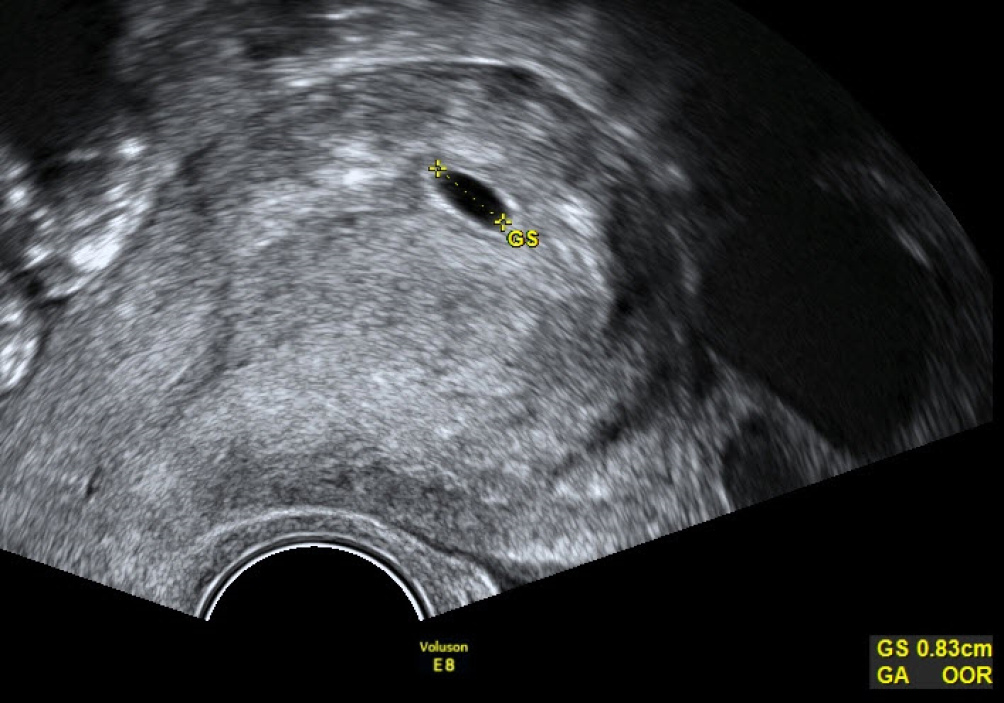

Bei gerade erst sichtbarem Fruchtsack muss dieser in drei Ebenen gemessen werden und der Mittelwert dann zur Berechnung herangezogen werden (Abb. 1).

Abb. 1

Ein 8 × 4 × 7 mm, im Mittel also 6 mm messender Fruchtsack in der Frühschwangerschaft noch ohne Dottersack und Embryo